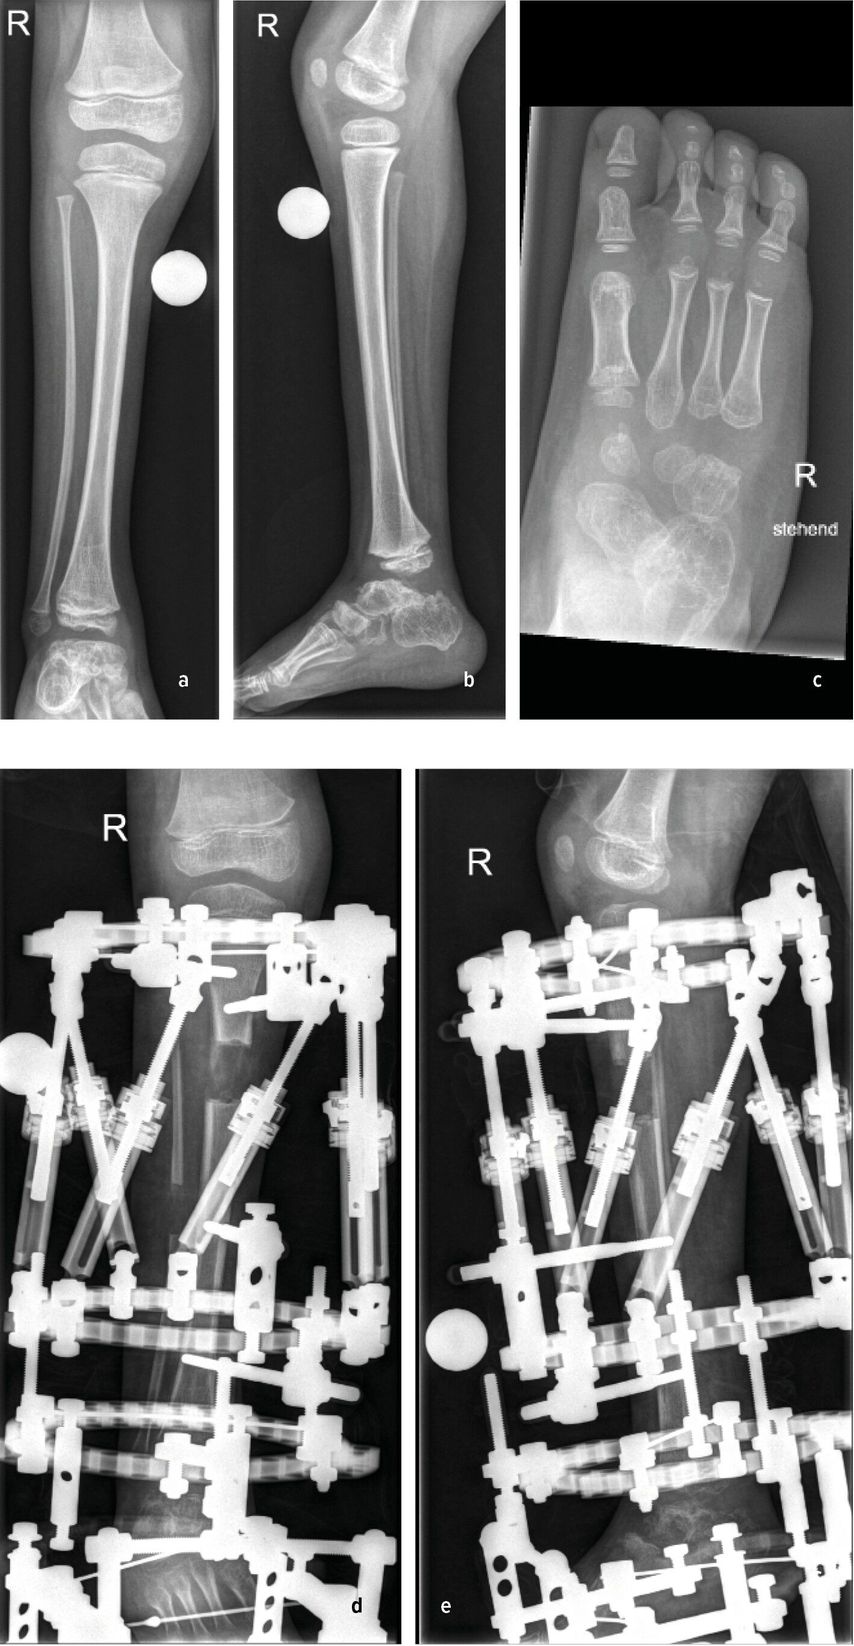

Anteromediales Bowing

Die Biegung der Tibia richtet sich in diesem Fall nach vorne und zur Körpermitte. Diese Fehlstellung tritt vor allem bei Fibulahemimelie in unterschiedlicher Ausprägung auf. Die fibuläre Hemimelie tritt bei 1:50000 bis 1:135000 Geburten auf. Der Phänotyp der Fibulahemimelie reicht von leichter Verkürzung bis zu einem Fehlen der Fibula und führt dadurch zu einem typischen anterioren oder anteromedialen Bowing des Unterschenkels. Instabilitäten des Knie- und Sprunggelenkes können mit der Fibulahemimelie einhergehen.1,2 Fußfehlbildungen gekennzeichnet durch das Fehlen der lateralen Strahlen, Koalitionen, Equinovalgus- oder Klumpfußstellung können auftreten. Anschaulich illustriert wird dieses Zustandsbild durch den klinischen Fall eines 6-jährigen Patienten mit unilateraler FH und 4-strahligem Fuß rechts sowie einer ausgeprägten Beinlängendifferenz vor chirurgischer Rekonstruktion. (Abb.1a–c).3 Die sporadische Form ist meistens unilateral und kann mit einem kongenitalen Femurdefekt einhergehen.1,4 Bilaterale Formen sind selten und treten häufiger im Rahmen von Syndromen auf. Eine Disruption in der frühen Embryogenese wird als wahrscheinlichste Ursache einer Fibulahemimelie angesehen, die Ätiologie ist jedoch unklar.1 Die am häufigsten verwendete Klassifikation nach Achterman-Kalamchi unterteilt die Fibulahemimelie in lediglich zwei Typen mit einer Subgruppe:5

Abb. 1: 6-Jähriger mit unilateraler FH und 4-strahligem Fuß rechts sowie ausgeprägter Beinlängendifferenz vor chirurgischer Rekonstruktion (a–c). Laufende Valguskorrektur und Beinlängenausgleich mittels externen hexapoden Fixateurs mit Fußeinschluss

Die neuere Unterteilung nach Paley bezieht die Sprunggelenkspathologien in die Klassifikation mit ein (vier Typen mit Untergruppen) und gibt auch hier Empfehlung zu operativen Verfahren ab.1 Ziele der chirurgischen Rekonstruktion umfassen die Fußkorrektur mit plantigrader Position, den Ausgleich der Beinlängendifferenz bei Wachstumsabschluss sowie eine neutrale Beinachse. Neben konservativen Maßnahmen wie Schuhzurichtungen und Orthosenversorgung, erfolgt die Korrektur schließlich über chirurgische Verfahren wie Stabilisierungstechniken des Knie- und Sprunggelenkes, Wachstumslenkung sowie beinverlängernde Maßnahmen. Im Fall des 6-jährigen Patienten erfolgten eine Valguskorrektur und ein Beinlängenausgleich mittels externen hexapoden Fixateurs und Fußeinschluss (Abb.1d,e).6 In besonders schweren Fällen mit ausgeprägter Fehlbildung und Hypoplasie des Fußes kann eine Amputation mit anschließender Orthoprothesenversorgung in Betracht gezogen werden.7